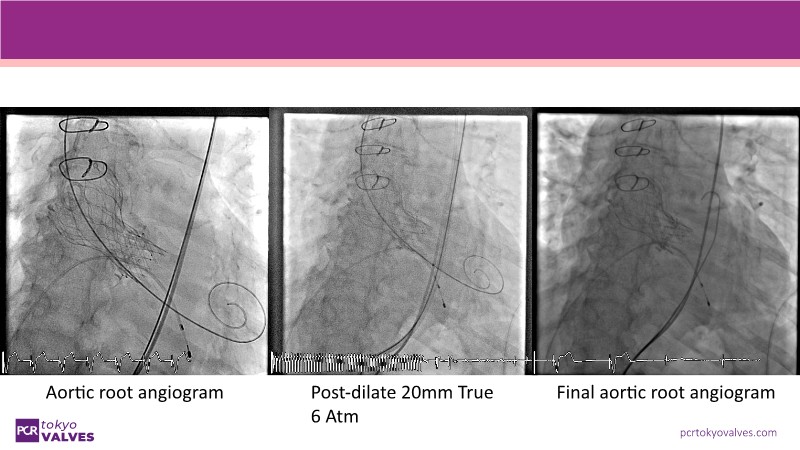

Watch this expert-led session on the latest Evolut TAVI advancements, device selection for small annulus cases, and strategies for complex anatomies. Learn about redo-TAVI feasibility and key 1-year data from the SMART trial.

• To master implantation techniques and discern the latest technological evolutions for treating patients with complex anatomies